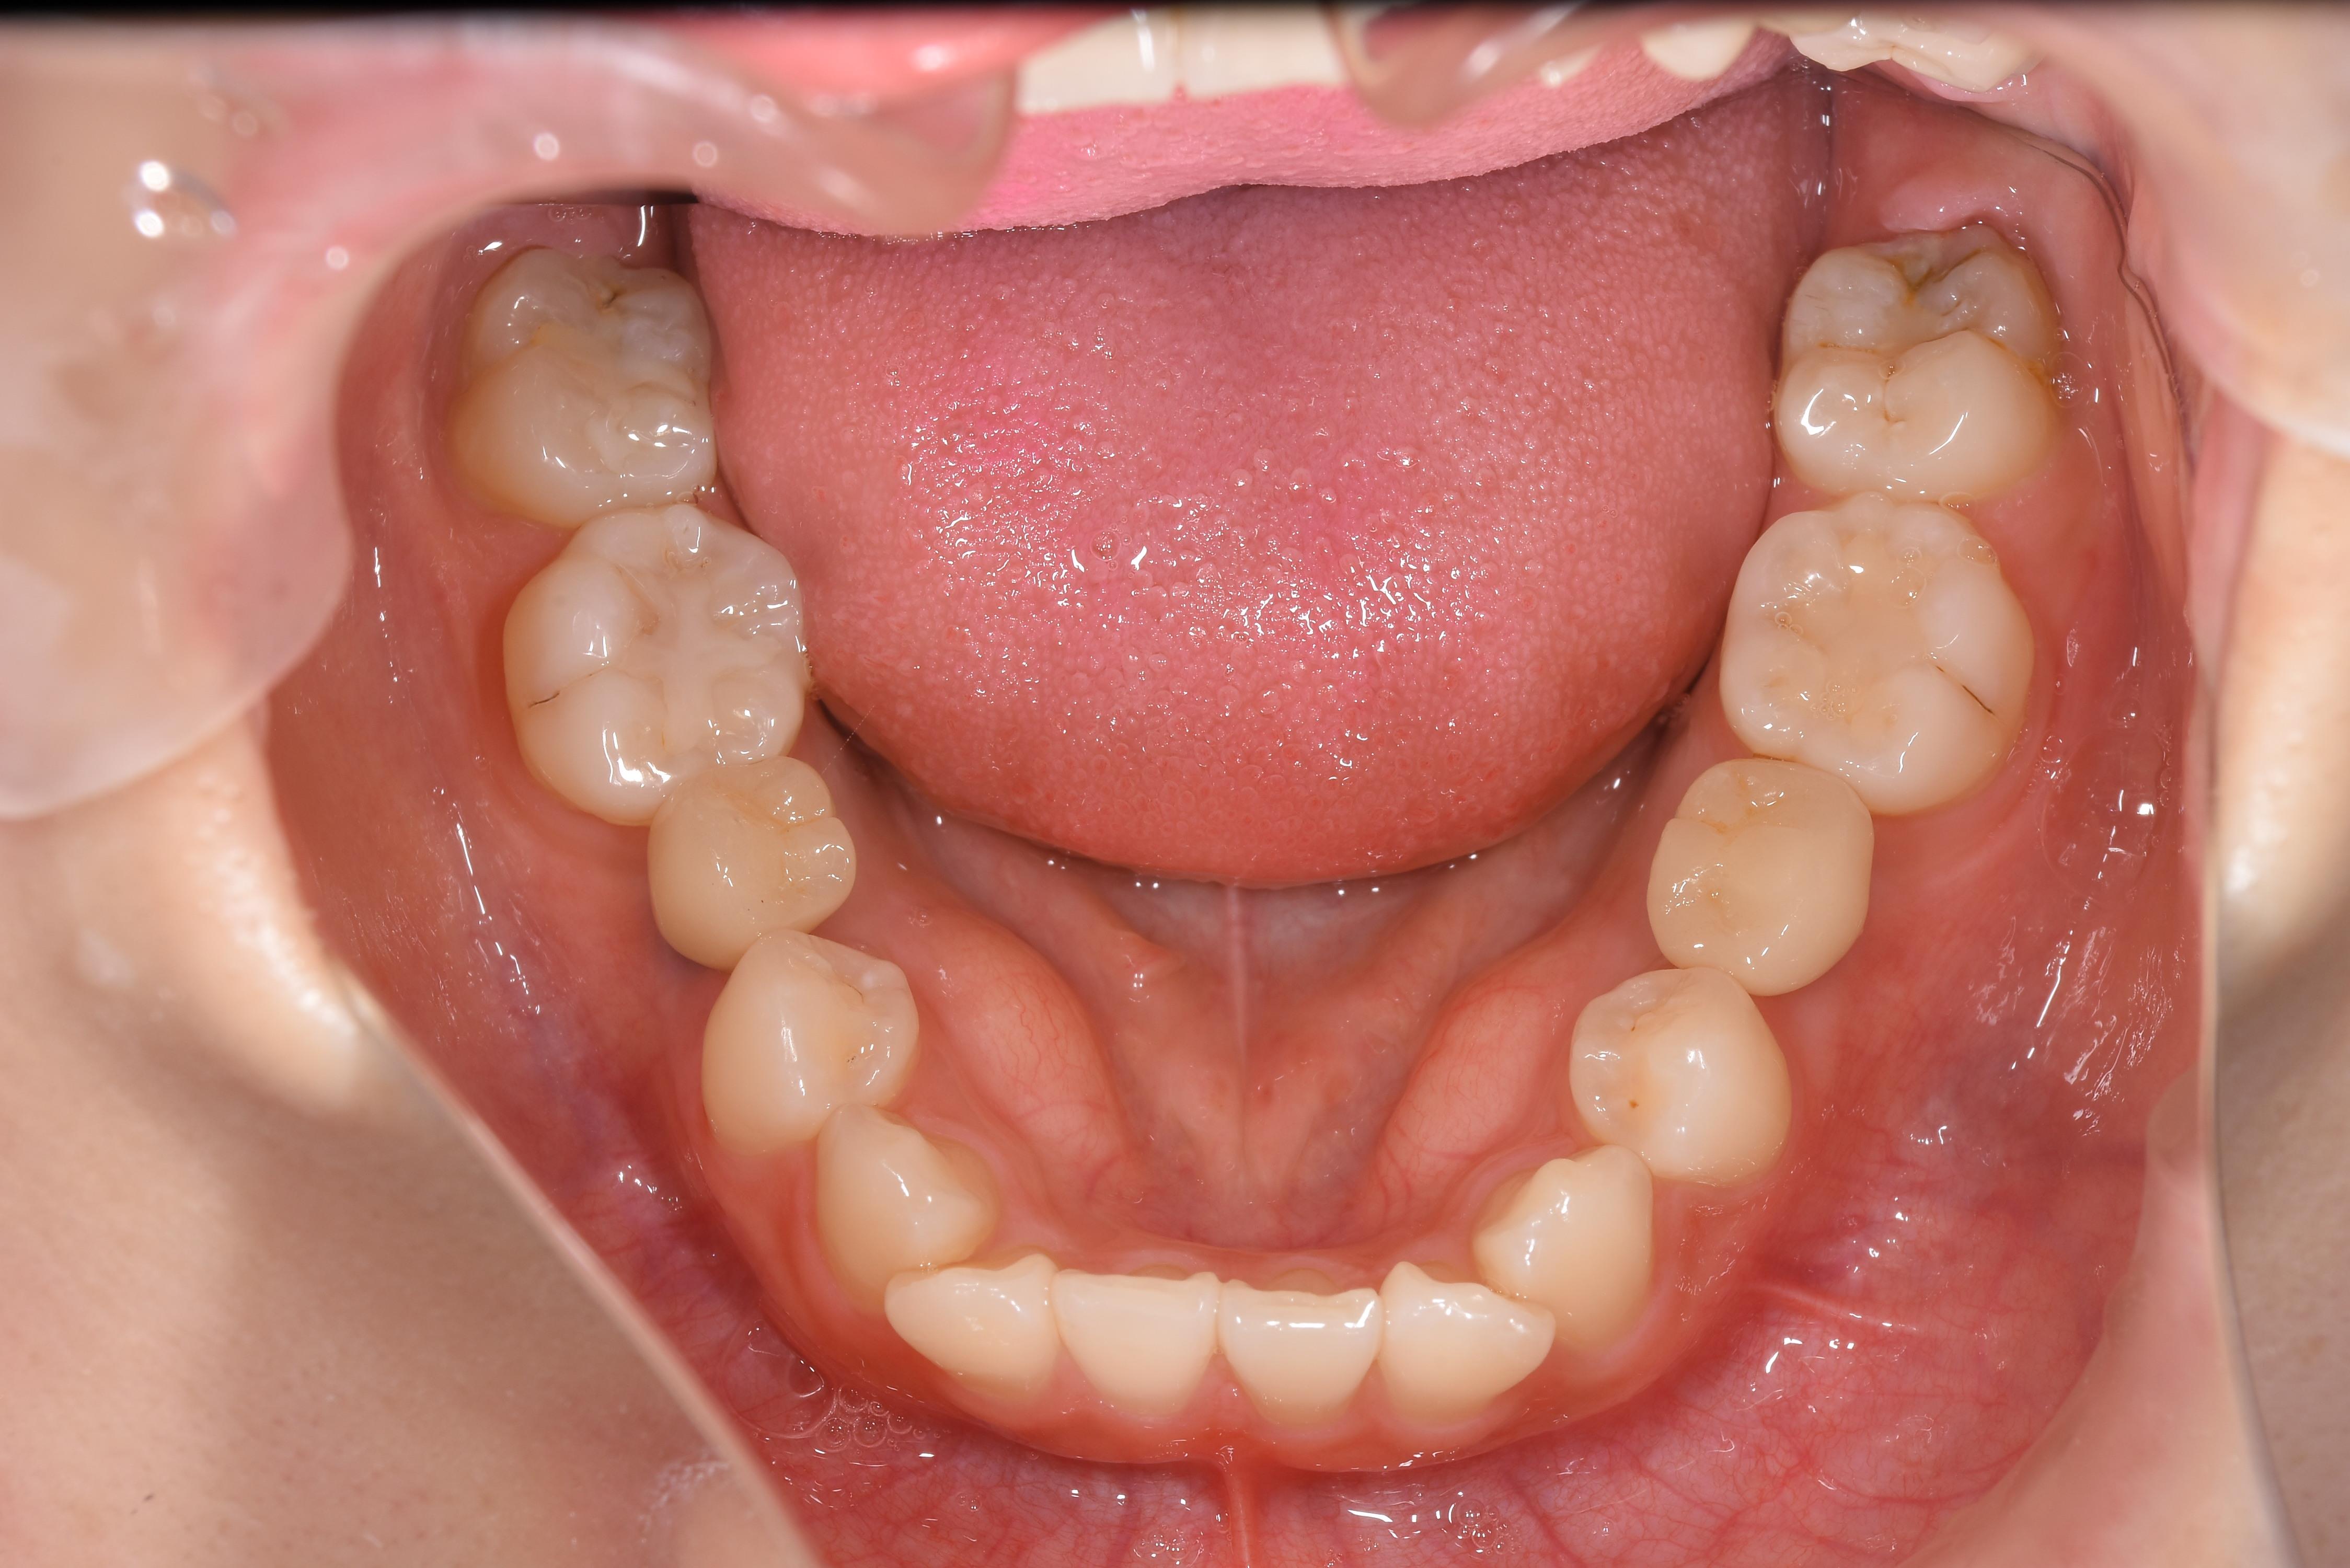

治療前

| 治療内容 | インプラント | 期間 | 4ヶ月 |

|---|---|---|---|

| 治療回数 | 10回 | 費用 | 880,000円(税込) |

| リスク 副作用 |

喫煙者・歯周病の方はインプラント生存率が著しく低下します | ||